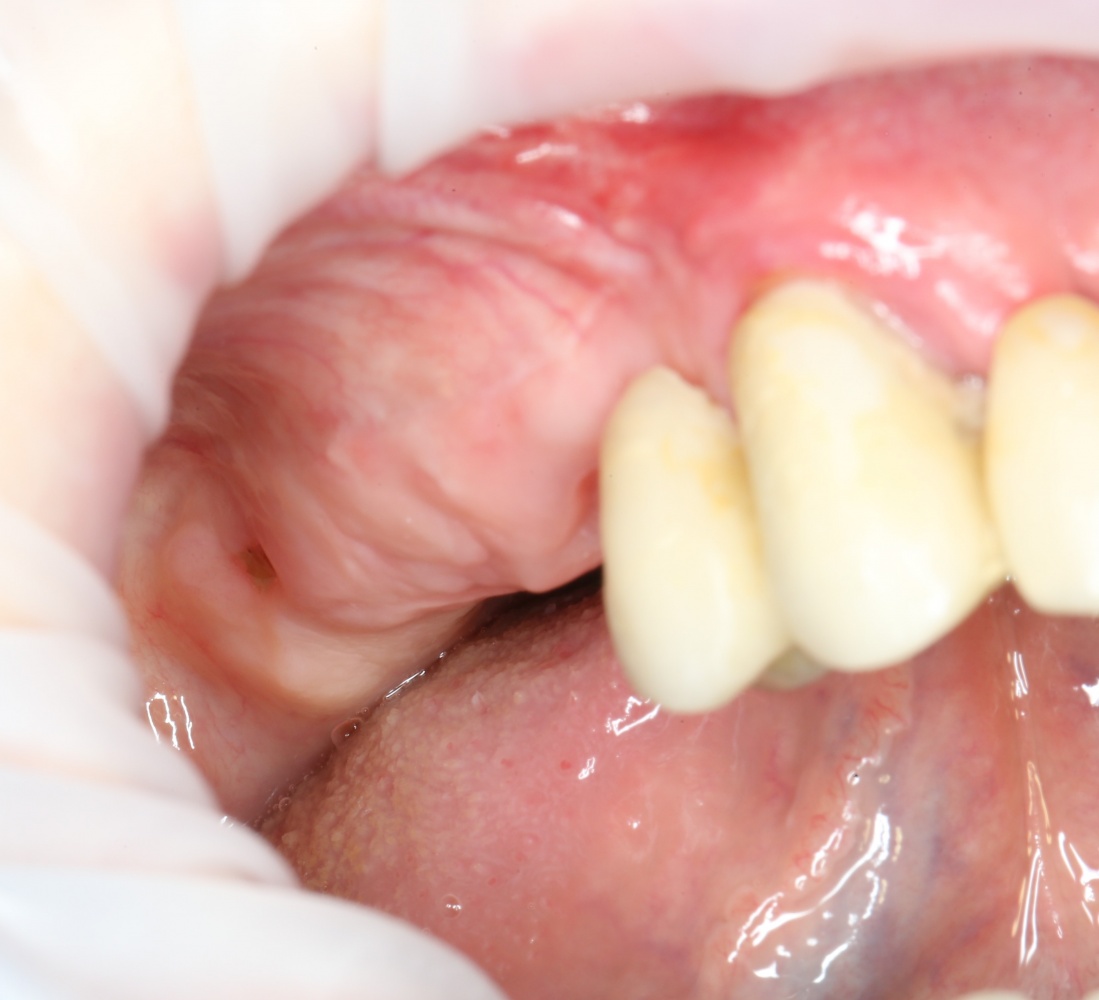

Вот клиническая картина через 4 месяца после ранее проведенной имплантации с остеопластикой:

Как видишь, коллеги из недалекой дружественной страны не осилили снятие швов. Мне это не нравится, хотя и объясняет, почему люди готовы ехать за тыщи километров ради 20-минутной операции удаления зуба мудрости.

Ну хорошо. Швы сняли. Делаем разрез. Обрати внимание, что после всех проведенных операций у нас остается очень небольшой по ширине слой жевательной слизистой оболочки: